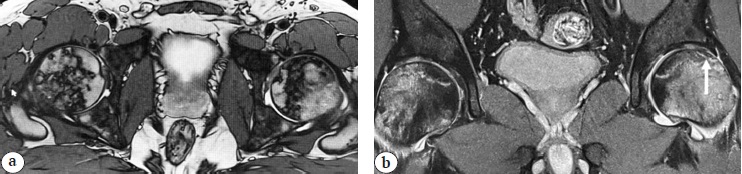

In patient 3, 120 days after the disease onset, hip joint pain appeared, and bilateral osteonecrosis of the femoral heads was diagnosed, that is, ARCO IIIC on the left and ARCO IIB on the right (Fig. 3).

Fig. 3. MRI signs of bilateral femoral head osteonecrosis in patient 3: left hip, ARCO IIIC stage; right hip, ARCO IIB stage; a — axial view; b — frontal view (an arrow shows the “crescent sign” that indicates the subchondral bone fracture)

At 4 weeks after bilateral osteonecrosis was diagnosed, due to the subchondral fracture of the head of the left femur (ARCO IIIC), patient 3 underwent total arthroplasty of the left hip joint.